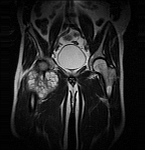

- Resection of benign and malignant tumors of the bone and soft tissue

- Tumor total endoprosthesis (TEP) of all large joints and bones

- Extensive reconstructive procedures for the reconstruction of large pelvic bone defects